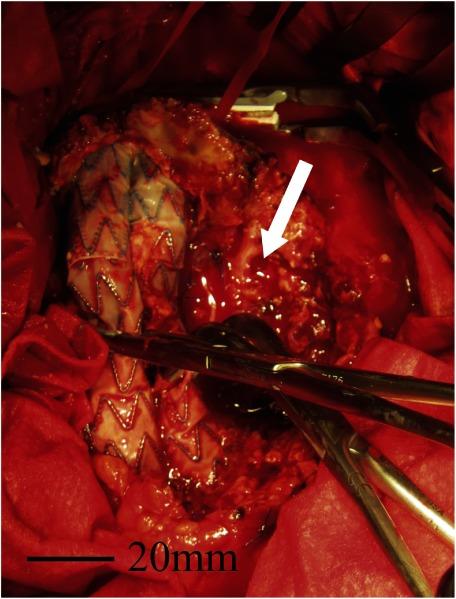

Listeria monocytogenes infection and rupture of the aneurysm sac, after endovascular aneurysm repair (EVAR), are both rare. We report the case of an 82-year-old man who presented with a ruptured aneurysm by infection with L. monocytogenes after EVAR. We successfully treated him by in situ reconstruction with a bifurcated expanded polytetrafluoroethylene (ePTFE) graft, with partial removal of the infected stent graft. At 30 months from the reoperation, the patient was in good health at home, with no symptoms of infection, and the gallium-67-citrate single-photon emission computed tomography/computed tomography (SPECT/CT) fusion images confirmed no fluid accumulation.

在血管内动脉瘤修复术(EVAR)后,单核细胞增生李斯特菌感染和动脉瘤囊破裂均较为罕见。我们报告一例82岁男性患者,其在EVAR术后因单核细胞增生李斯特菌感染出现动脉瘤破裂。我们通过使用分叉型膨体聚四氟乙烯(ePTFE)移植物进行原位重建,并部分移除感染的覆膜支架成功治疗了该患者。再次手术后30个月,患者在家中健康状况良好,无感染症状,枸橼酸镓-67单光子发射计算机断层扫描/计算机断层扫描(SPECT/CT)融合图像证实无积液。